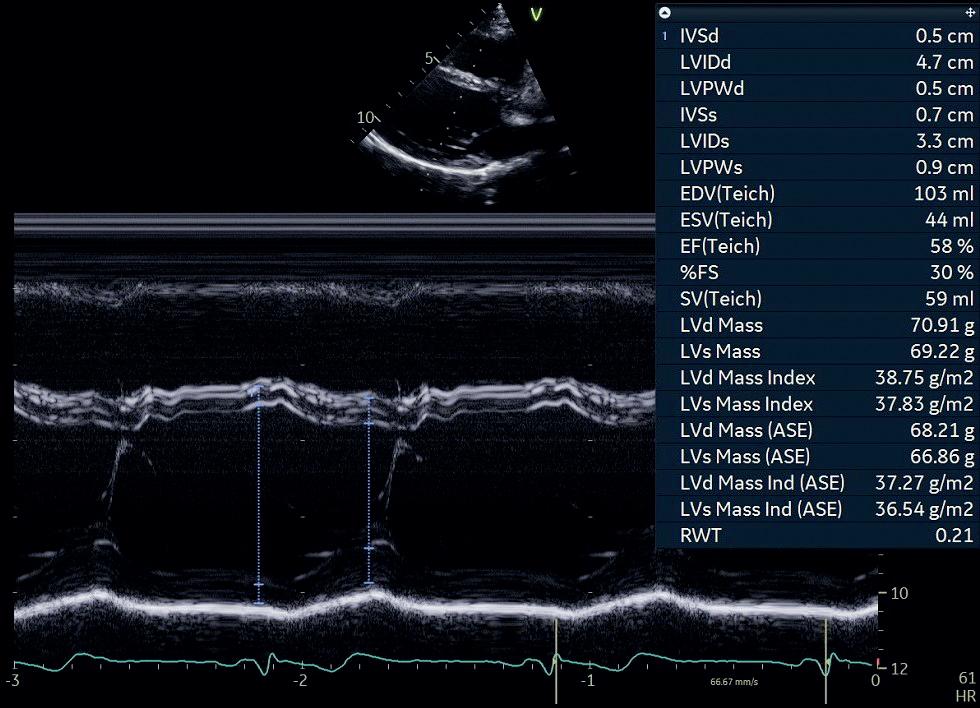

Ved M-modusekkokardiografi (M for motion) er det kun én krystall i transduseren som sender ut og mottar ultralydimpulser i rask rekkefølge. Pulsrepetisjonsfrekvensen er > 1 000/s, som gir en svært god tids- og dybdeoppløsning. Strukturer som beveger seg, vil fremtre som kurver på skjermen, og kombinert med registrering av EKG kan bevegelsene til strukturene vi studerer, tidsrelateres til hjertesyklus (figur 1.4).

Dersom vi klarer å unngå vinkelfeil, kan M-modusekkokardiografi brukes for eksempel til måling av dimensjoner og veggtykkelser, og for å studere hjerteklaffenes bevegelse.

Figur 1.5: 2D-ekkokardiografi av hjertet i apikal 4-kammerprojeksjon Venstre ventrikkel er kammeret øverst til høyre Legg merke til at ventrikkelveggen er særlig tykk mot apex (piler) Dette er et eksempel på apikal hypertrofisk kardiomyopati (HCM) med det såkalte ace of spades-tegnet Figur 1.4: M-modusekkokardiografi i parasternal langakseprojeksjon med markørlinjen gjennom venstre ventrikkel Eksempelet viser måling av ventrikkelens veggtykkelser og indre diameter, som muliggjør estimering av blant annet ventrikkelmassen